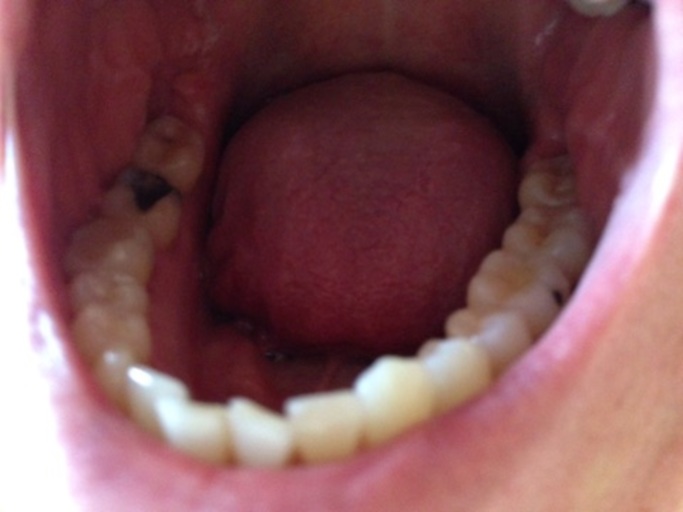

Hello, after I got braces and started wearing elastics I noticed the sharp point of one of my top teeth was grinding into the hole in one of my bottom teeth. So the sharp point (like that on a canine) is digging into the crevice in the surface of my bottom tooth. Won't the friction cause an even larger hole or cavity and wear down my teeth? My own dentist said that it wouldn't, but I'm still really worried because I dont get how it wouldn't be an issue. Thank you!